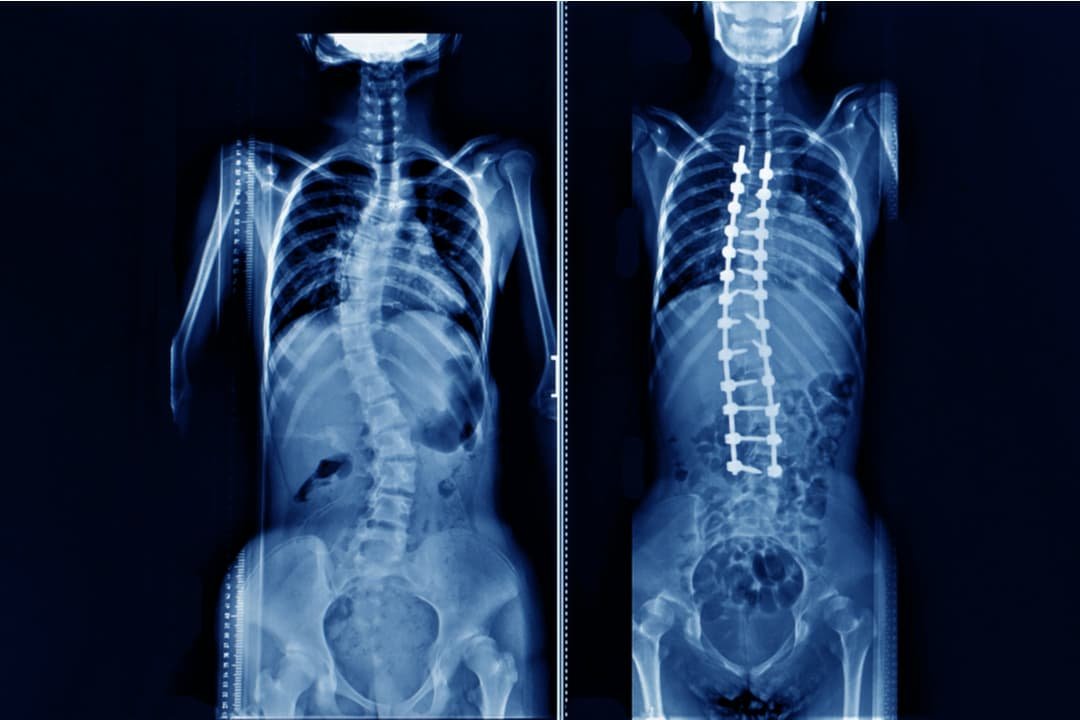

Scoliosis